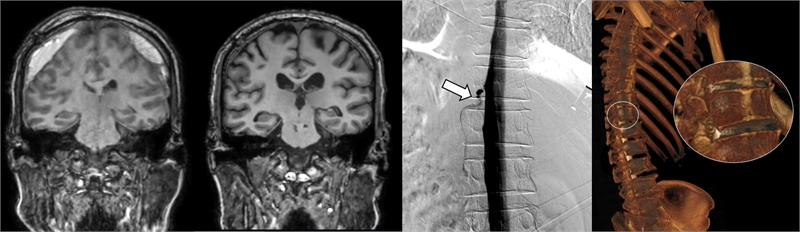

▲ (왼쪽) DSM으로 확인한 누공 위치, (오른쪽) 측위 CT 척수 조영술로 확인한 뇌척수액 정맥 누공 3D 영상

세브란스병원은 최근 DSM을 국내 최초로 도입해 이와 같은 기존 진단법의 한계를 극복했다. DSM(Digital Subtraction Myelography, 디지털 감산 척수조영술)은 척수에 조영제를 주입하고 모니터 화면으로 뇌척수액의 흐름을 실시간으로 확인할 수 있다. 이를 통해 뇌척수액이 새나가는 구멍을 정확하게 찾아낼 수 있게 됐다.

DSM과 더불어 세브란스병원이 함께 진행 중인 측위 CT 척수 조영술까지, 모두 뇌척수액 정맥 누공을 진단할 수 있는 최신 기법이다.

이번에 세브란스병원을 찾은 환자들은 DSM 검사와 측위 CT 척수 조영술로 뇌척수가 새어나가는 부위를 정확히 진단‧치료받고, 뇌압을 회복했으며 경막하출혈도 사라졌다. 이에 따라 환자들이 보였던 인지기능 저하와 보행장애도 모두 호전됐다.